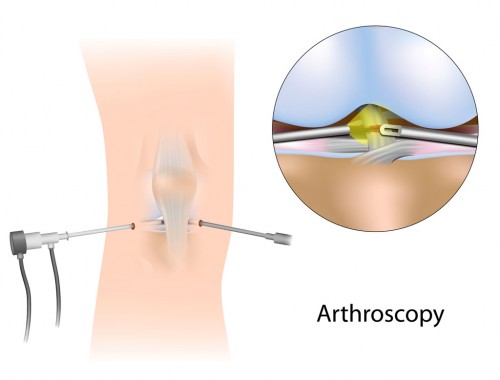

Shoulder Arthroscopy

Similar to the knee, arthroscopy in the shoulder was first used for diagnostic purposes before being expanded to include therapeutic purposes. A variety of disorders affecting the shoulder joint can be evaluated by orthopedic surgeons using the minimally invasive shoulder arthroscopy procedure.